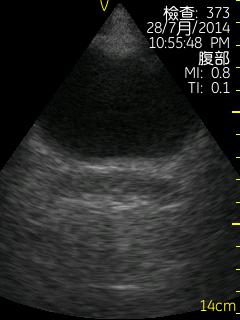

Vscan临床图片 腹部